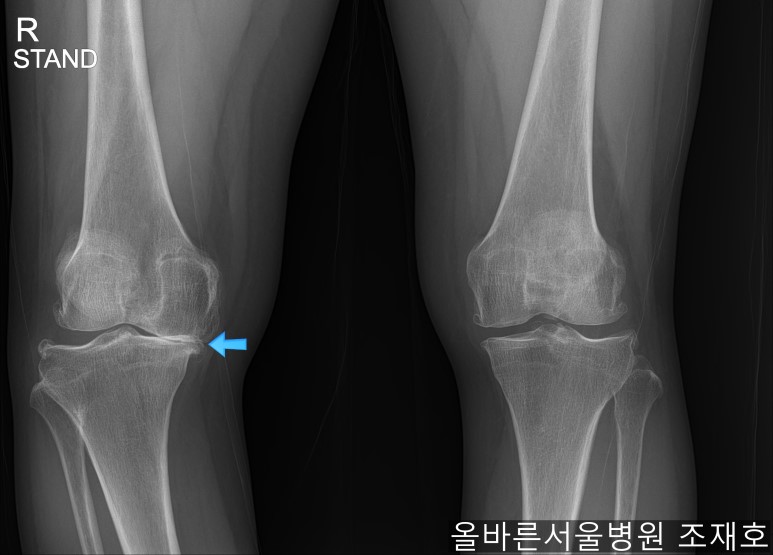

仅通过放射线片子观察到:右膝由于炎症严重,内侧胫骨及股骨已接触在一起,向内测严重变形。

左膝虽然也观察到了炎症,但远不如右膝严重。

如果通过X光片也观察到相同的病症,可以判断内侧关节的软骨大部分都损伤了。

观察膝盖下肢排列的扫描图像可看到右腿严重变形,身体中心向内倾斜。